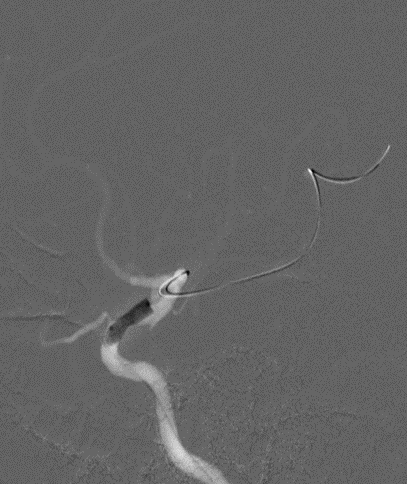

导引导管到位,导丝通过病变。

导丝怎么扩【载药时代 球扩天下】NOVA DES®颅内药物洗脱支架在颈内动脉颅内段重度狭窄中的应用体会二例!_https://www.jmylbn.com_新闻资讯_第7张

球囊通过病变。

导丝怎么扩【载药时代 球扩天下】NOVA DES®颅内药物洗脱支架在颈内动脉颅内段重度狭窄中的应用体会二例!_https://www.jmylbn.com_新闻资讯_第8张

球囊扩张过程。

导丝怎么扩【载药时代 球扩天下】NOVA DES®颅内药物洗脱支架在颈内动脉颅内段重度狭窄中的应用体会二例!_https://www.jmylbn.com_新闻资讯_第9张

扩张后造影。

导丝怎么扩【载药时代 球扩天下】NOVA DES®颅内药物洗脱支架在颈内动脉颅内段重度狭窄中的应用体会二例!_https://www.jmylbn.com_新闻资讯_第10张

支架通过病变。

导丝怎么扩【载药时代 球扩天下】NOVA DES®颅内药物洗脱支架在颈内动脉颅内段重度狭窄中的应用体会二例!_https://www.jmylbn.com_新闻资讯_第11张

支架释放。

导丝怎么扩【载药时代 球扩天下】NOVA DES®颅内药物洗脱支架在颈内动脉颅内段重度狭窄中的应用体会二例!_https://www.jmylbn.com_新闻资讯_第12张